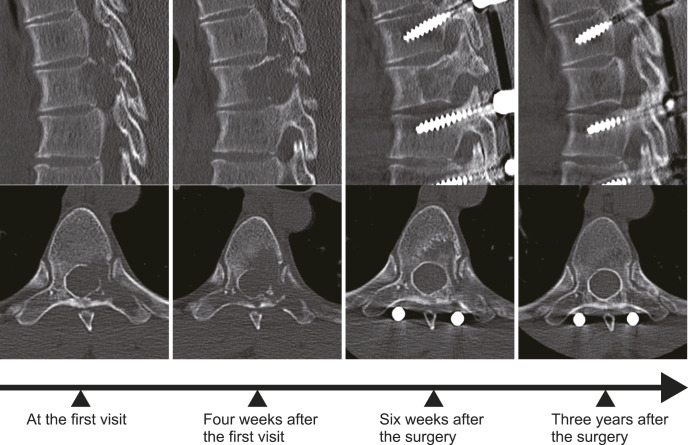

Results: Four male patients aged between 21 and 28, each with a single spinal LCH lesion (T6, T5, and C5) except one case (T5 and T7), were treated. Diagnoses were confirmed via biopsy (two open, two needle biopsies). Whole-body computed tomography or bone scintigraphy revealed no additional LCH lesions in any patient, except in one patient with a small lung nodule. All patients presented with severe back or neck pain and pathological fractures at the affected vertebra. Thoracic LCH cases received percutaneous pedicle screw fixation, while the cervical case was managed with conventional posterior instrumentation using lateral mass screws. After surgery, all patients experienced significant pain relief, halted bone lysis, and rapid new bone formation. One patient underwent chemotherapy postsurgery. Over 3 years of follow-up, imaging studies revealed no recurrences of the disease.

Conclusions: Posterior instrumentation, without the need for curettage or bone grafting, is a promising surgical treatment for adult spinal LCH. This method may effectively halt lesion progression, prevent spinal deformity, and avert neurological deficits in the patients with progressive spine lesion where conservative treatment may not adequately prevent vertebral fractures.